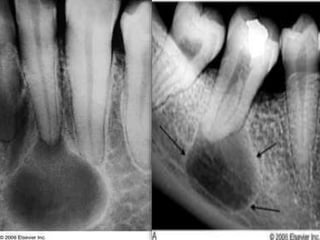

Condensing Osteitis

 4% to 8% of population

 Focal areas of radiodense sclerotic bone

 Mandible, apices of first molar

 Reactive bony sclerosis to pulp inflammation

 Irregular, radiopaque

 Stable, no treatment required

Condensing Osteitis  4%to 8% of population  Focal areas of radiodense sclerotic bone  Mandible, apices of first molar  Reactive bony sclerosis to pulp inflammation  Irregular, radiopaque  Stable, no treatment required